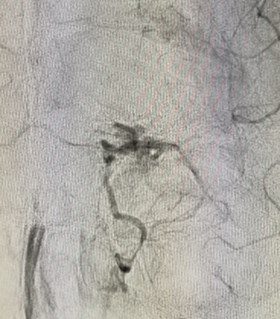

Nuovo angiografo biplanare

Eccezionale intervento su bambino

Rara malformazione artero-venosa al cervello